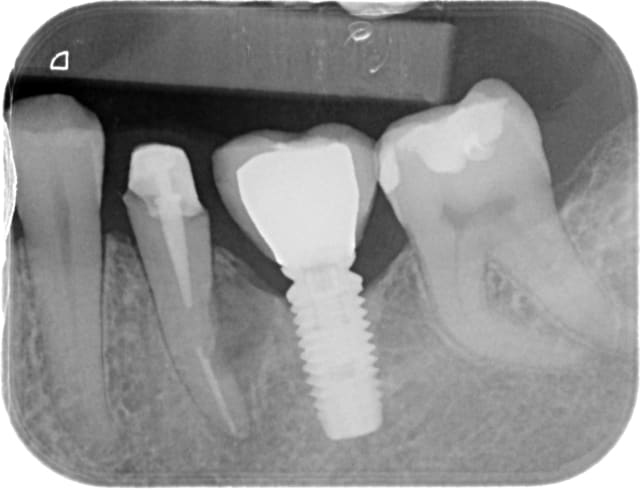

photos jointes: cas de resorption externe avec à l'origine faux canal, félure ou juste la resorption qui avait atteint le canal...

Obturée à la biodentine allongée, pose de srew post titane dans la foulée de l'obturation, un moignon compo a été réalisé ensuite.

Dent traitée en urgence (abcès), ça saignait mais j'ai pu cauteriser (merci lokki), une galère si j'avais voulu mettre de la gutta.... perdue pour perdue j'ai tenté le truc, c'était en janvier 2014 et la dent, recoiffée depuis est toujours là, asymptomatique.

La patiente est prevenue que ça tiendra ce que ça tiendra et qu'elle doit faire des economies pour eventuel implant à venir (ou vacances avec son copain si l'implant tarde à venir).